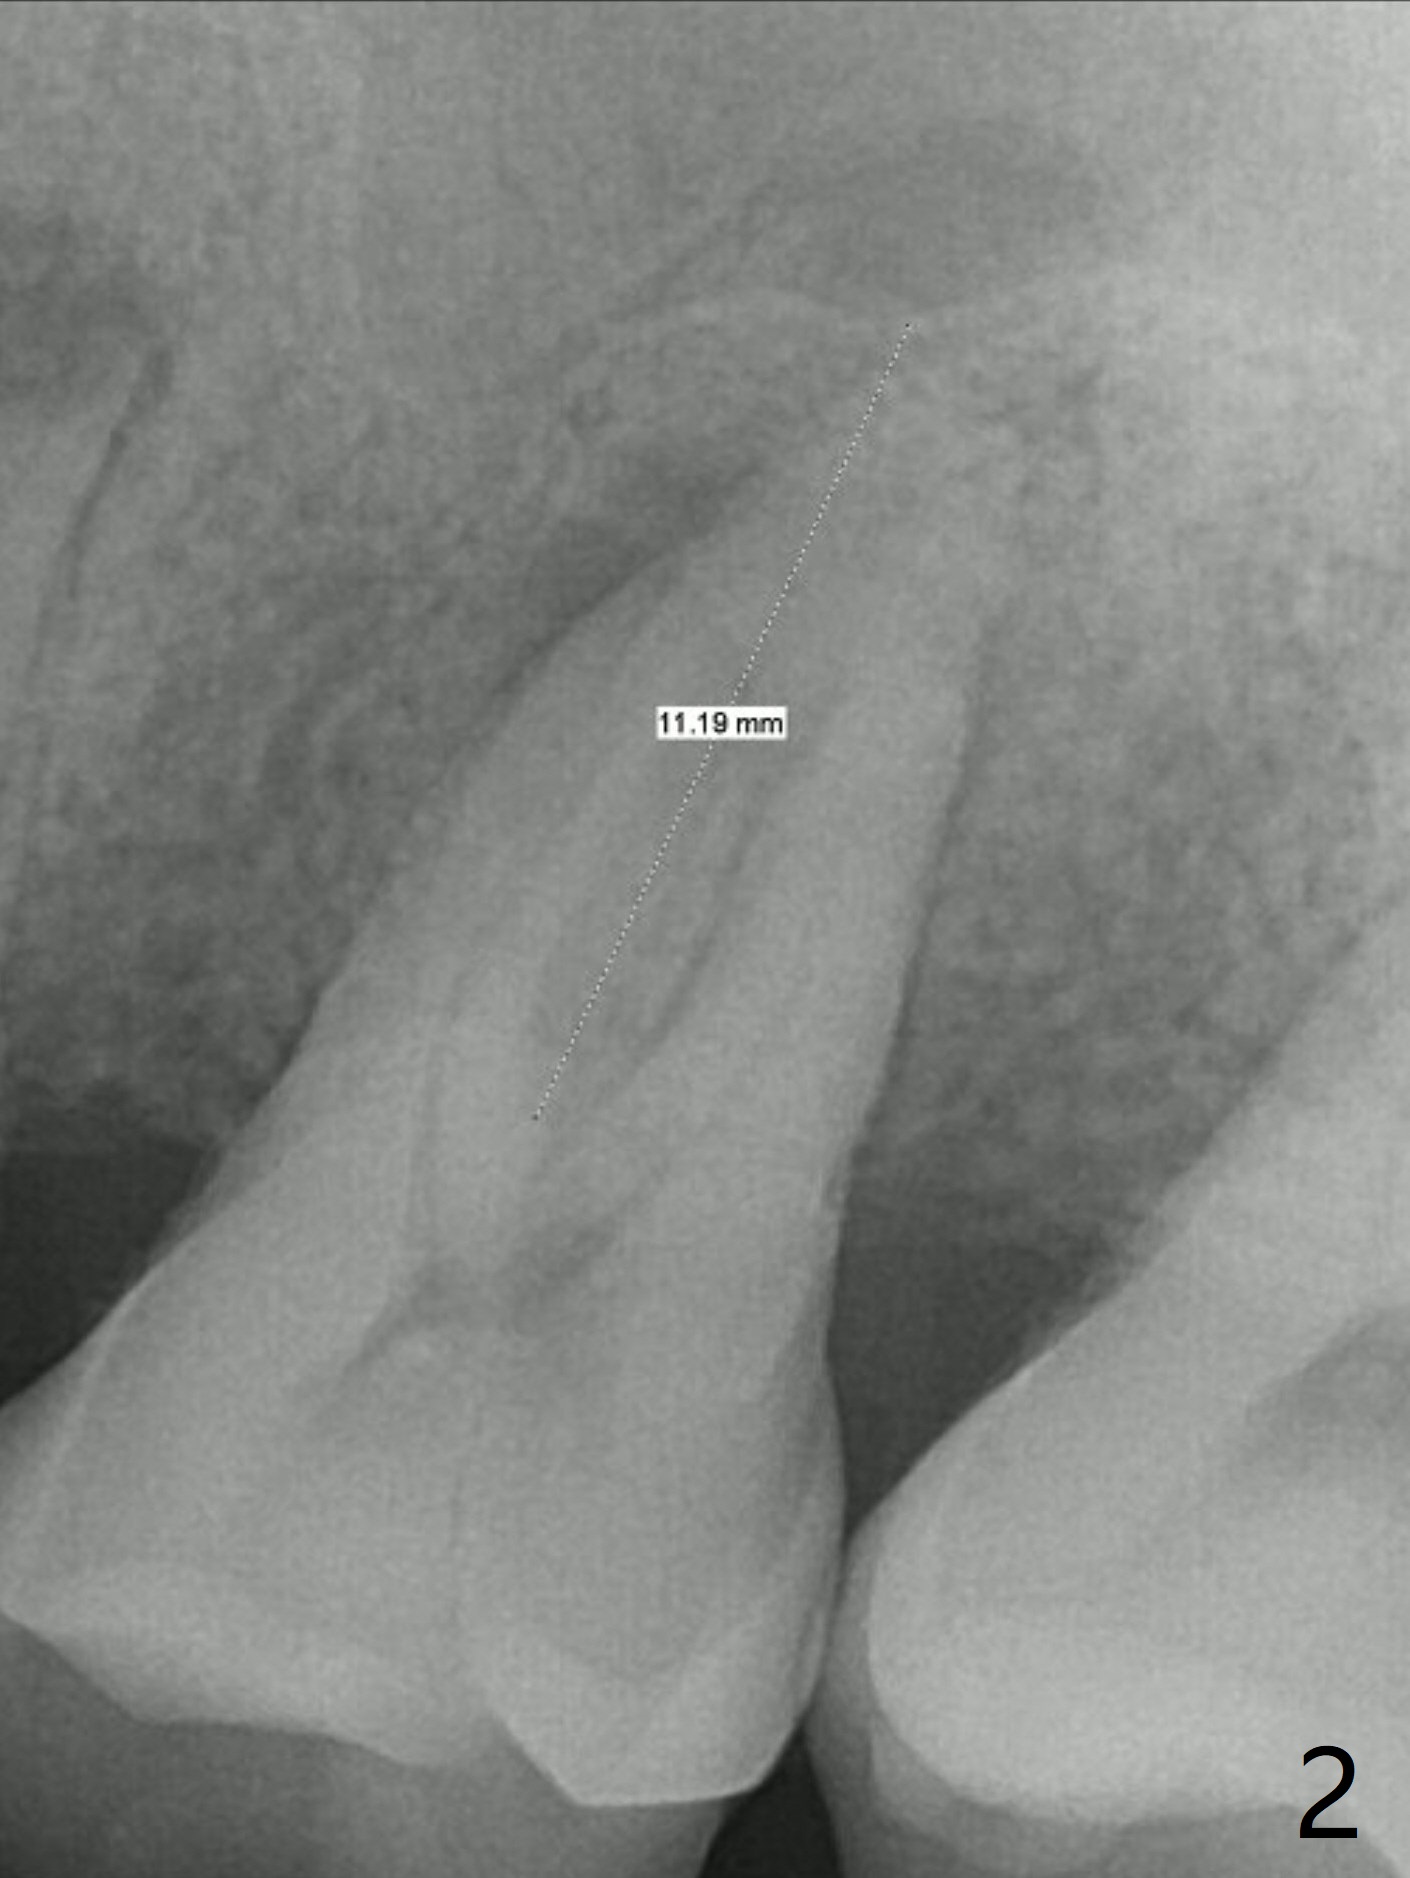

A 45-year-old man has chronic generalized moderate localized severe periodontitis; gingival recession is severe lingual of the tooth #14 with mobility II (Fig.1). The low bone density outline (Fig.1 white dashed line) is larger than the roots, suggesting lingual bone loss/low lingual crest. Although the bone height seems to be 11 mm (Fig.2), the bone responsible for primary stability of an implant will be apical (Fig.3 *,4). The implant platform will be ~3 mm subcrestal buccal, while ~3 mm supragingival lingual (Fig.5). The diameter of the implant will not be too large, 4.5 mm (dummy). There will be not biologic width issue. The large perimplant gap will be closed with sticky bone. Severe palatal gingival recession is shown pre- (Fig.6) and post- (Fig.7) SRP. #30 Gutta Percha inserted palatal reaches the highest point of the low bone density lesion (Fig.8). Pulpal test and CT will determine that endodontic treatment can regrow bone or that socket preservation is needed with Cytoplast.